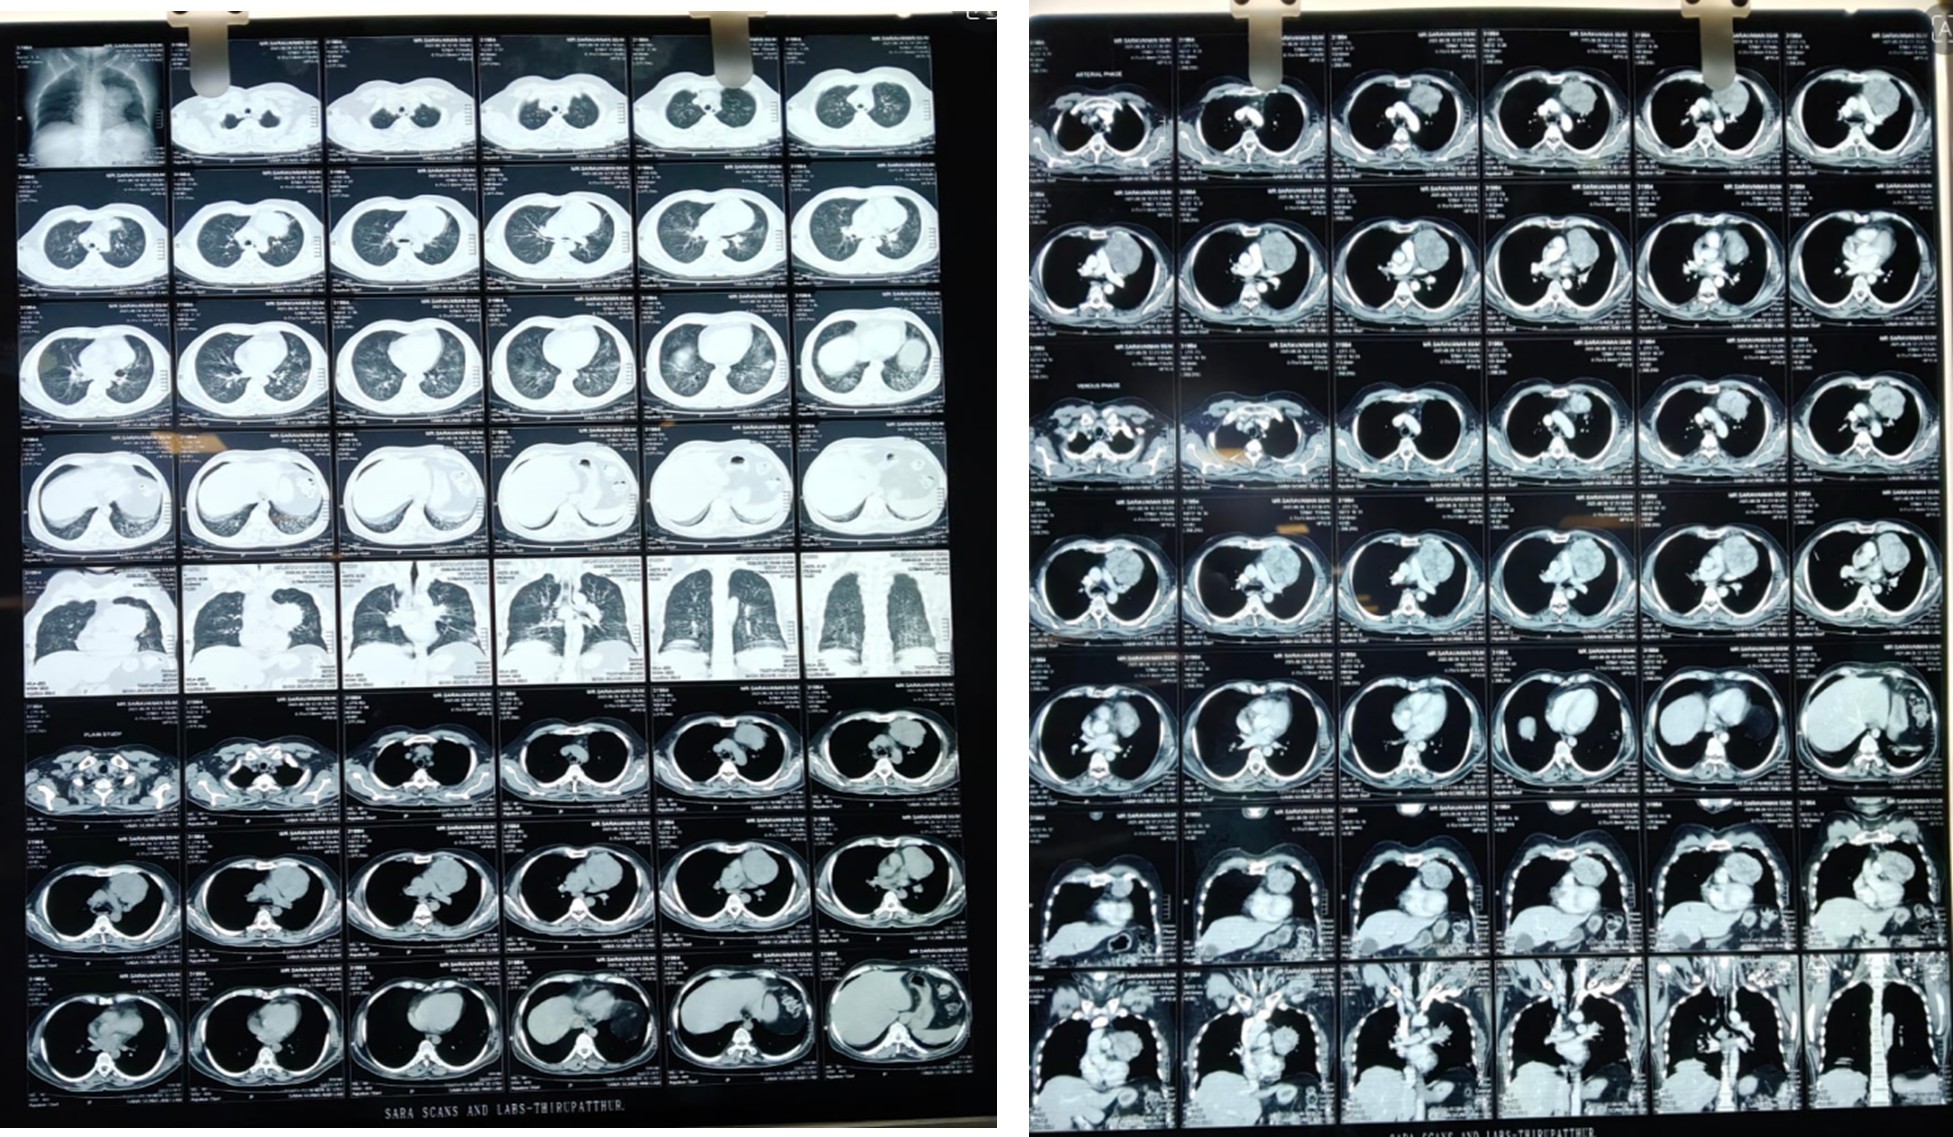

Relevant Investigation: CT chest

• Relatively well defined large heterogeneously enhancing soft tissue density mass lesion in left upper anterior mediastinum.

• Imaging features are in favor of Thymoma (for HPE correlation).

• Diffuse randomly distributed centrilobular nodules in both lung fields with few of them coalescing to from foci of consolidations in posterior & lateral segments of left lower lobe.

• Imaging features are in favor of co-existing atypical pneumonitis.

Radiological Findings

• Ct chest showed a large, heterogeneously enhancing soft tissue mass in the left anterior mediastinum

• Features suggestive of thymoma.